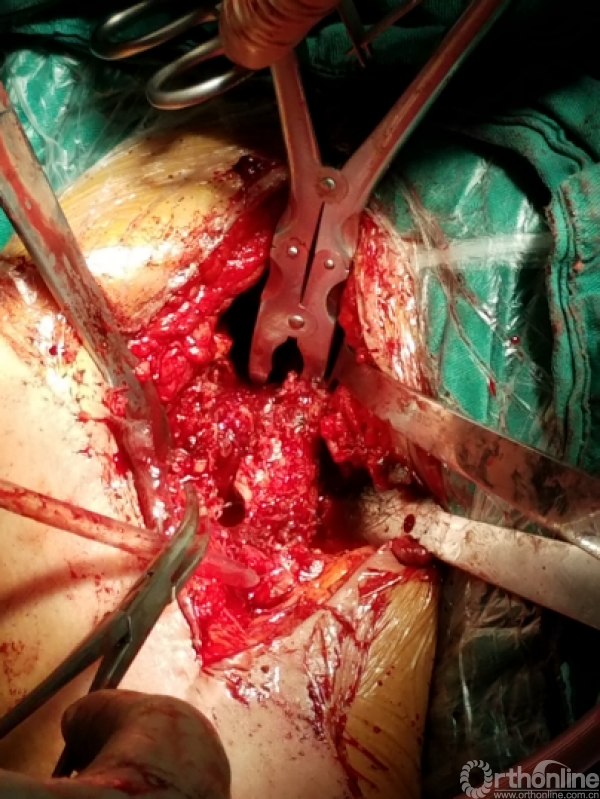

显露出肱骨头假体柄处

开始向内上扩大显露

注意事项:  肱骨头内移至喙突处,位于后内侧下方已有骨桥连接

特别小心腋鞘及臂丛神经

提示无法顺利脱位!!!

小心咬出间隙后,牵引肘关节前屈肩关节后伸外旋,拉钩撬拨脱位!!

关节盂正常结构消失,至喙突偏内侧部位,上方紧贴肩峰下,仍然有骨质可用!

咬除连接骨桥,清理髓腔,恢复活动度

1.关节盂正常结构消失,前倾增大。

2.紧贴喙突内侧

3.骨质菲薄

4.特别小心肌皮神经及腋鞘

骨质疏松明显,皮质成虫蚀样改变,外侧缺损。